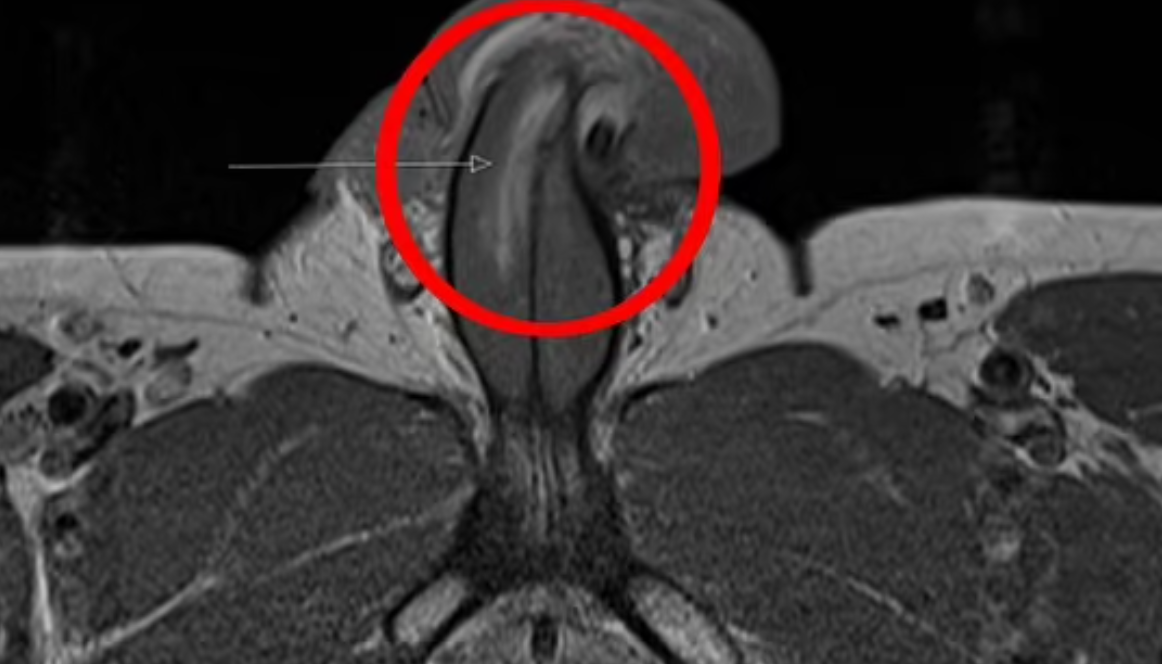

Πρόκειται για την πρώτη καταγεγραμμένη περίπτωση κατάγματος πέους που ήταν σε όρθια στάση και δημοσιεύθηκε στο British Medical Journal. Σύμφωνα με την ιατρική αναφορά, το πέος του άνδρα κυριολεκτικά «τσάκισε» σαν καλαμάκι λόγω κακού συγχρονισμού με την σύντροφο του. Οι γιατροί δεν είπαν σε ποια θέση βρισκόταν, αλλά τα κατάγματα του πέους προκαλούνται συνήθως όταν ο άνδρας είναι από πάνω ή σε «doggy style», έγραψαν στην έκθεση.

O 40χρονος μάλιστα δεν είχε καταλάβει ότι κάτι έσπασε αλλά άκουσε ένα «κρακ» και σταδιακά έπεσε η στύση του. Πάντως πρέπει να θεωρεί τον εαυτό του τυχερό γιατί οι χειρουργοί κατάφεραν να αποκαταστήσουν χωρίς επιπλοκές την λειτουργία του μορίου του και μετά από έξι μήνες ήταν και πάλι απόλυτα λειτουργικός.